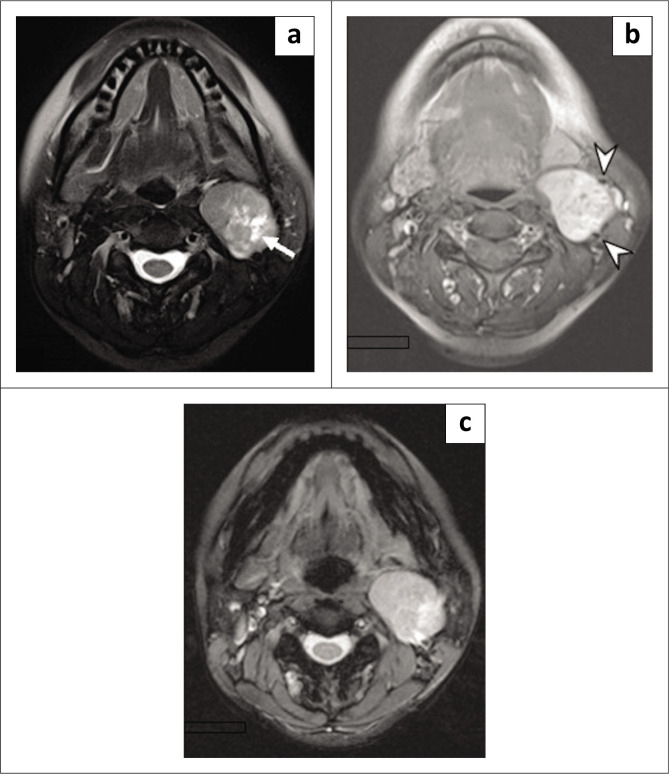

Nerve sheath tumours of the sympathetic chain are extremely rare and present a diagnostic challenge. A 42-year-old female presented with asymptomatic left cervical swelling. Imaging with sonography, CT, MR and angiography demonstrated a lesion splaying the carotid bifurcation, the lyre sign. Following surgical excision, histology revealed a schwannoma. Imaging features of carotid body tumours and parapharyngeal schwannomas can be similar, as both can cause splaying of the carotid bifurcation. The differential diagnosis of such tumours and their management are discussed.

Contribution: This article highlights another cause of the lyre sign on radiological imaging besides carotid body tumours.